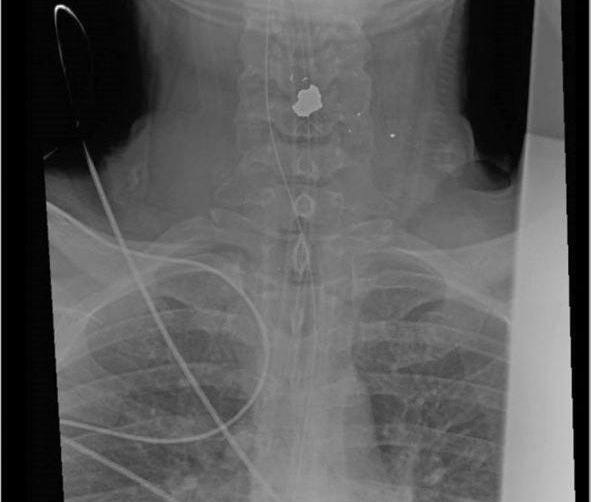

There are so many questions out there that TPUSA (Andrew Kolvet - who is Charlie’s executive producer and business partner) has been forced to respond to questions about why there was no exit wound on Charlie’s neck if he was shot in front.

Kolvet responded by saying that the surgeon said that the bullet went in through the front of the neck and did NOT exit at all. They say it hit Charlie's bone (neck vertebrae) and stopped and was found just under the skin. That's why they say there was no exit wound and no blood spatter behind.

If there WERE an exit wound in the back of his neck - from a Mauser .30-06 round - it would have been HUGE, correct?

Yeah, I’m still not buying that his neck bone stopped the bullet they say caused his death. Just saying…something else is going on here IMHO. This is just a random X-ray of what they say happened.

TPUSA and the media are going with the theory that the shot came from 140 yards away from a Mauser 30.06 and penetrated the neck but was stopped by bone and lodged next to the skin and that Charlie is a MAN OF STEEL. This narrative doesn’t seem logical to me at all. This is only 15 minutes long and it’s the best summary I’ve seen of where we are at regarding Charlie’s murder...without hyperbole and clickbait hysteria. It’s worth your time.